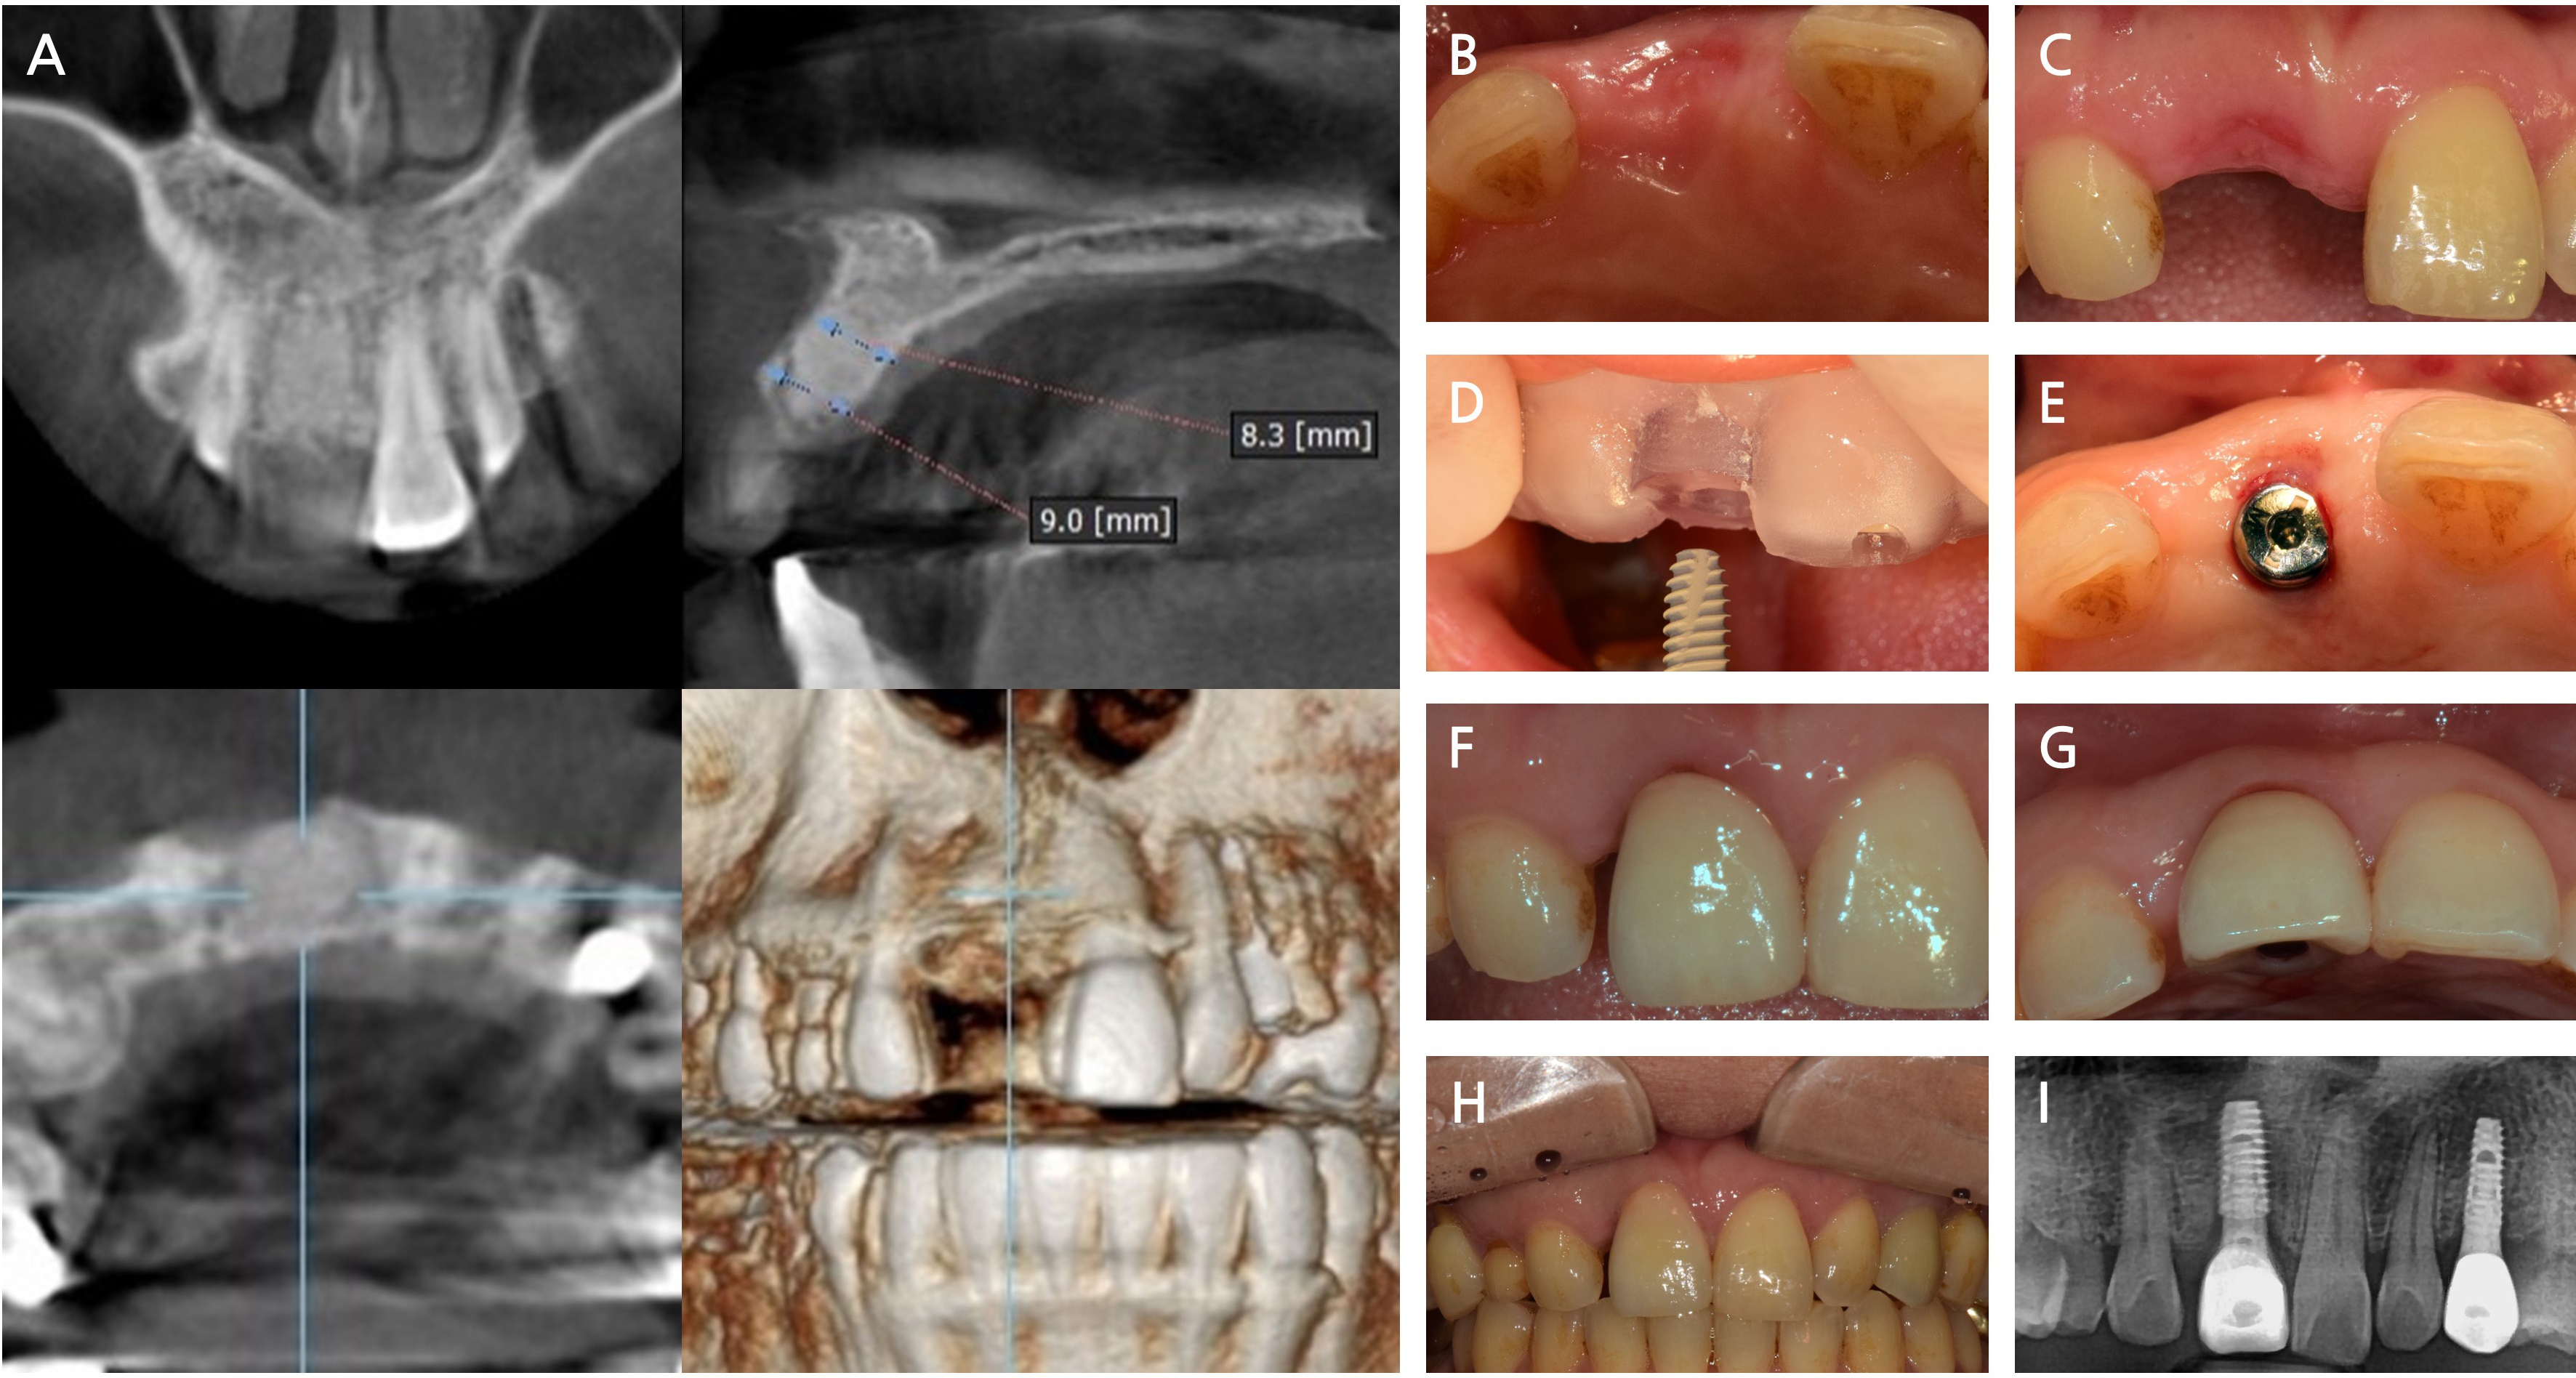

- Recombinant Human Bone Morphogenetic Protein-2 Loaded Acellular Dermal Matrix in Horizontal Ridge Augmentation: Two Cases

- Hyo-Eun Pak, Jeong-Rae Seo, Hye-Jun Seo, Jang-Ho Son

- Horizontal ridge deficiency in the posterior mandible often necessitates augmentation to achieve optimal implant placement and ensure long-term functional success. Although recombinant …

- Horizontal ridge deficiency in the posterior mandible often necessitates augmentation to achieve optimal implant placement and ensure long-term functional success. Although recombinant human bone morphogenetic protein-2 (rhBMP-2) and acellular dermal matrix (ADM) have individually been explored for bone regeneration, their combined clinical use—especially under functional loading—remains limited. This report presents two clinical cases involving horizontal ridge augmentation using rhBMP-2-loaded ADM without the use of additional grafting material. Radiographic evaluations at 5–6 months postoperatively confirmed horizontal bone gains of 1.5 mm and 1.7 mm, respectively. The newly formed bone was continuous with the adjacent native bone and fully covered the previously exposed implant threads. No postoperative complications, including peri-implantitis or peri-implant mucositis, were observed during the 13- and 10-month follow-up periods. - COLLAPSE